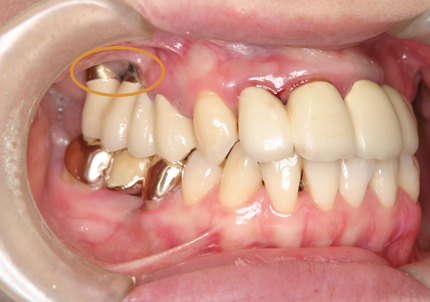

1.初診時口腔内(2007年6月30日)

2.右側上顎洞サイナスリフト後にインプラント埋入

↑ サイナスリフト術前